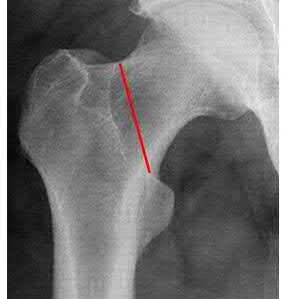

Which of the following is a recognized predictor of mortality after hip fracture?

American Society of Anesthesiologist (ASA) classification is predictive of post-surgical mortality in hip fracture patients.

The ASA classification (detailed in Illustration A) was initially developed in 1963 and has been shown to be predictive of post-surgical mortality in hip fracture patients. Basic categories are as follows: 1= normal, healthy; 2= mild systemic disease; 3= severe systemic disease, not incapacitating; 4= severe incapacitating systemic condition, constant threat to life; 5= moribund patient; 6 = brain dead, organs being donated.

Richmond et al. looked at 836 patients treated for a hip fracture and found that this injury is not associated with significant excess mortality among patients older than age 85. However, in younger patients, those with ASA classifications of 3 or 4 have significant excess mortality following hip fracture that persists up to 2 years after injury.